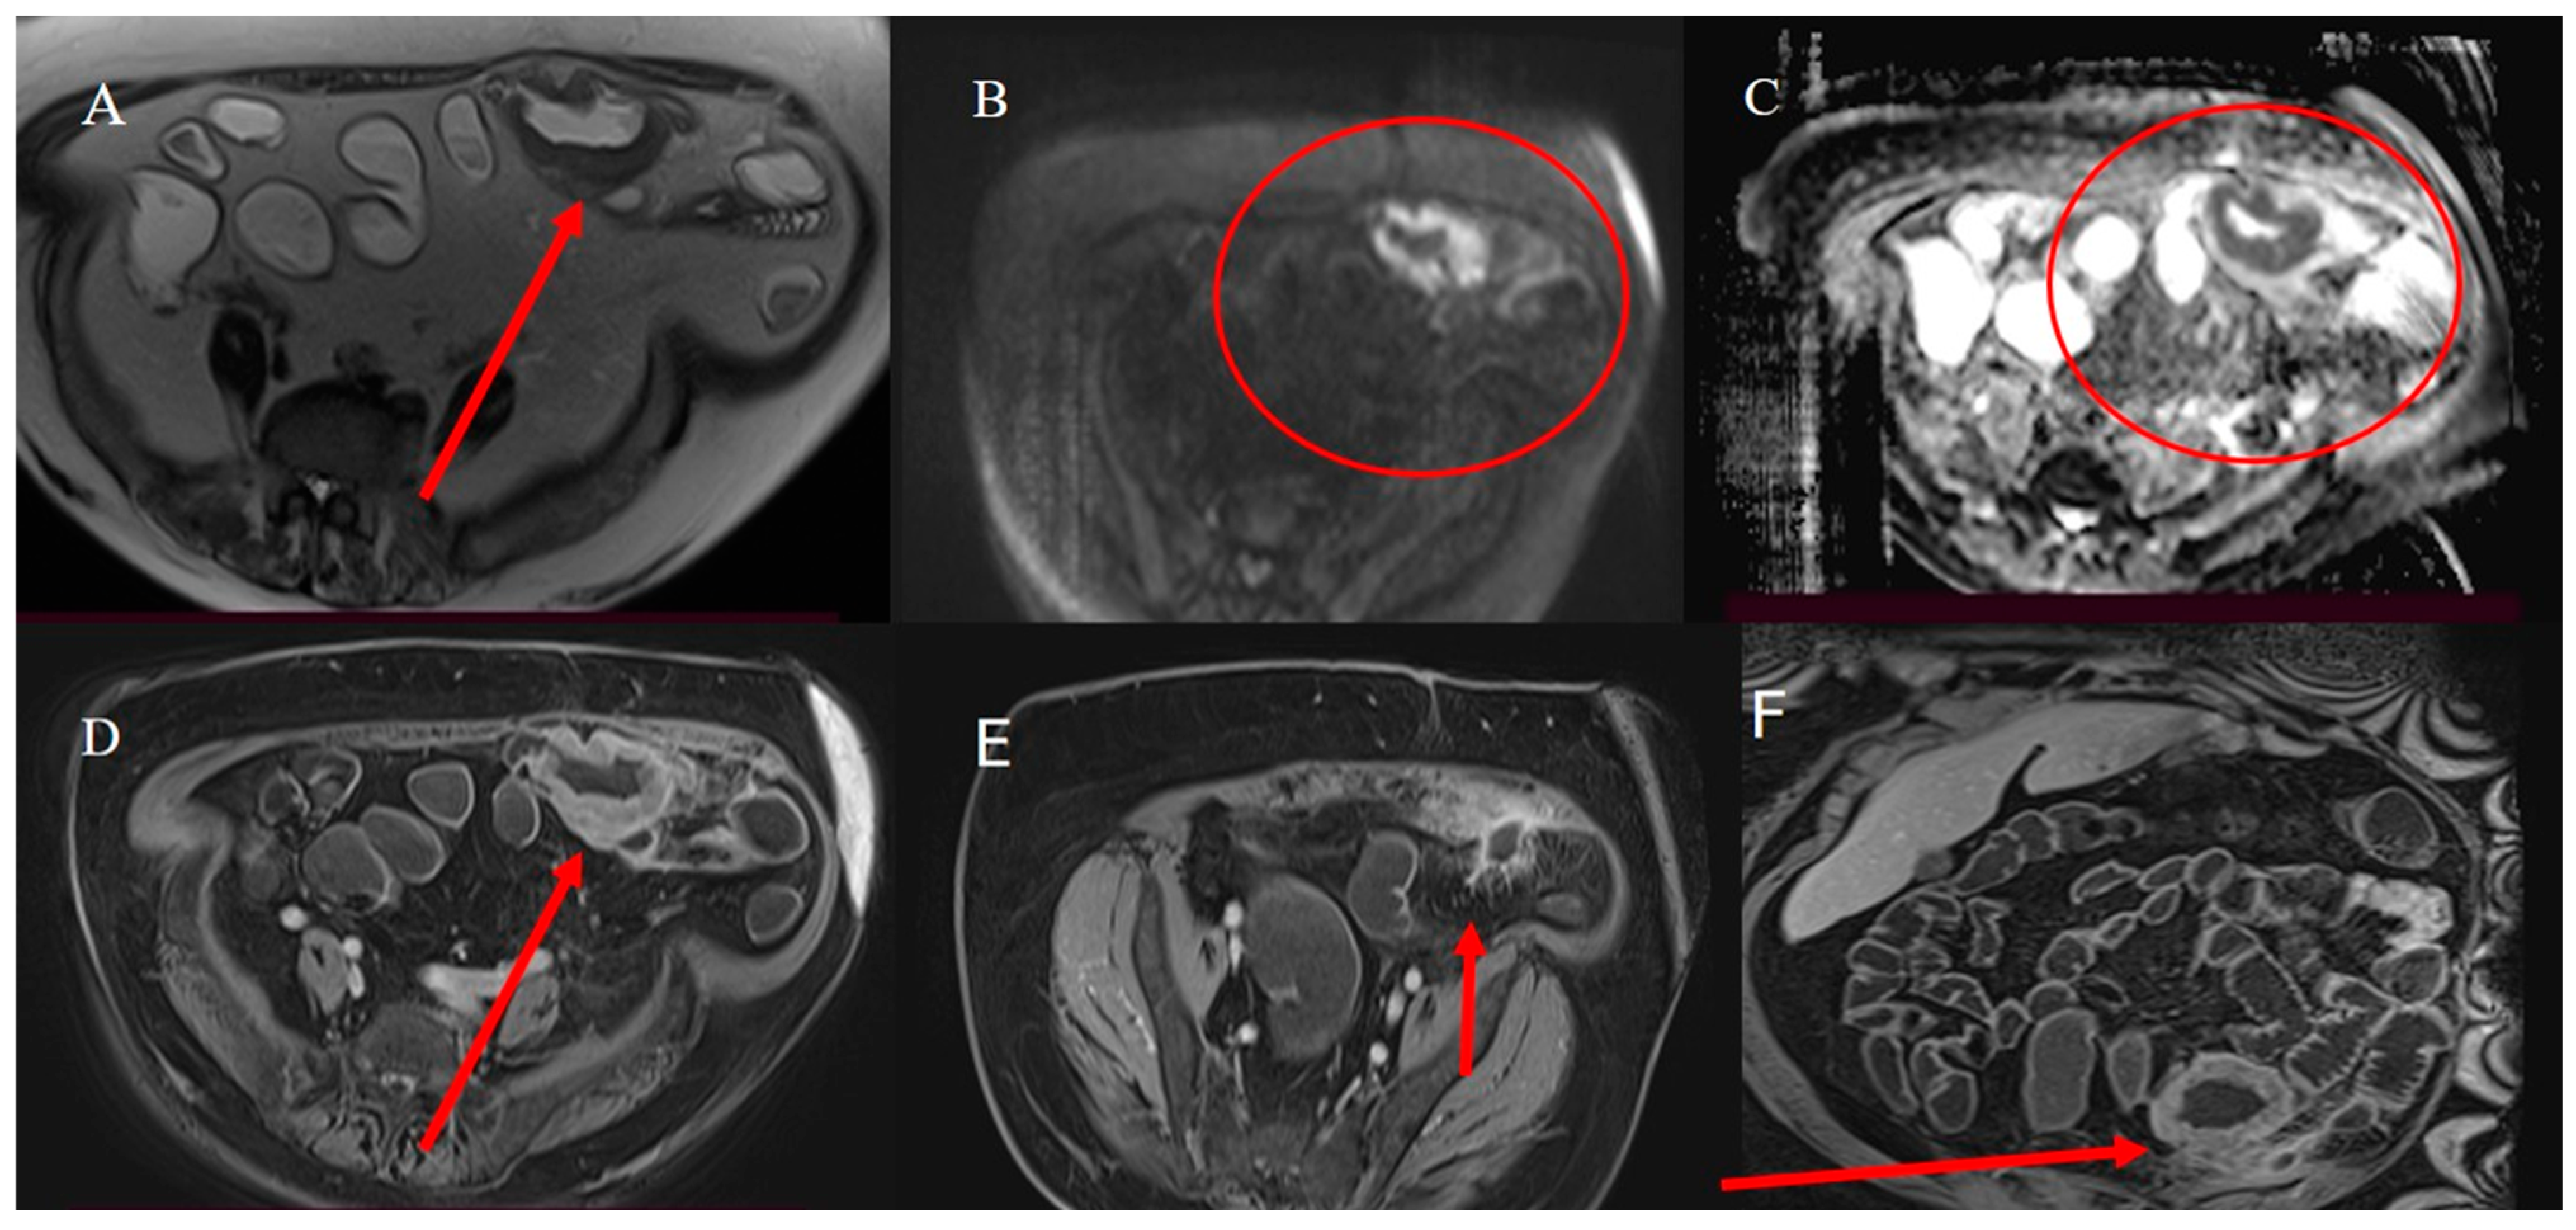

- Paparo, F.; Panvini, N.; Montale, A.; Pigati, M.; Marinaro, E.; Melani, E.F.; Piccardo, A.; Molini, L. Multimodality imaging features of small bowel cancers complicating Crohn’s disease: A pictorial review. Abdom. Radiol. 2024, 49, 2083–2097. [Google Scholar] [CrossRef]